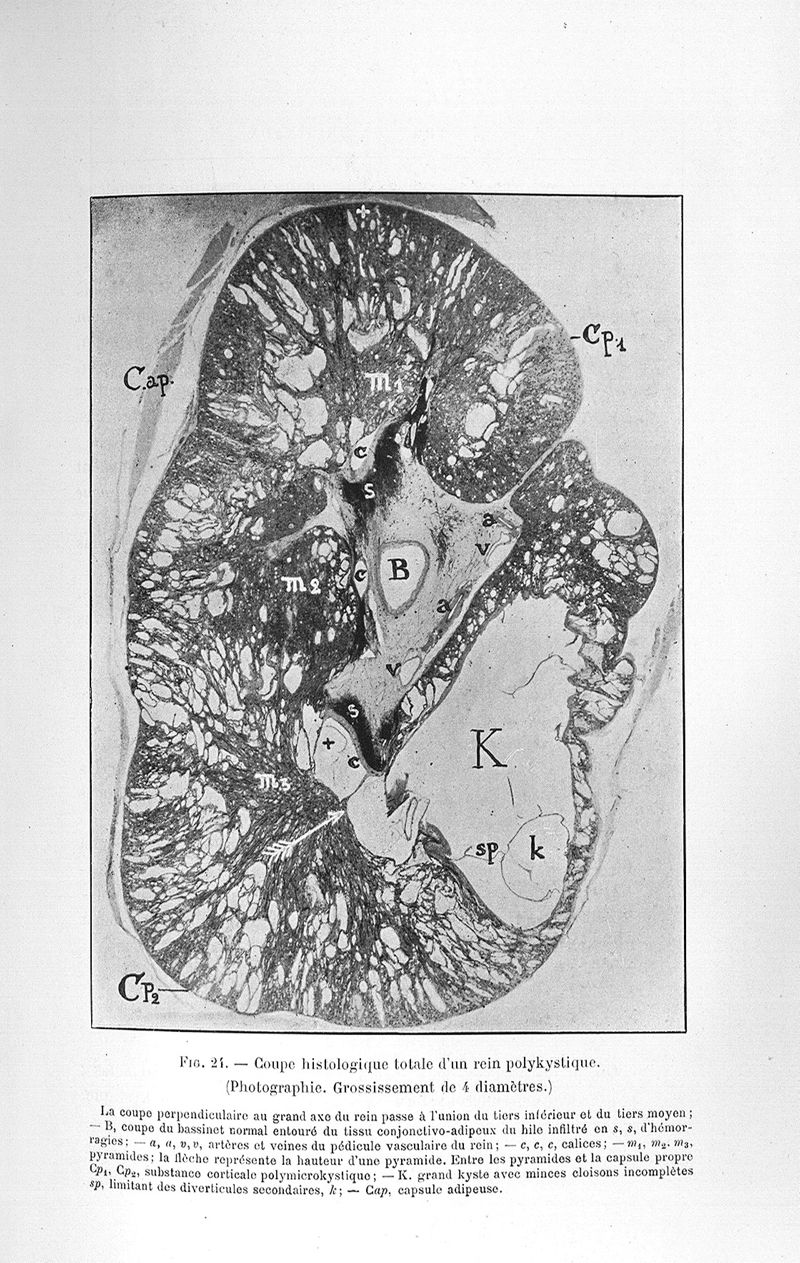

Couvelaire, Alexandre Adrien M..

Exposé des travaux

Paris, G. Steinheil, 1904.